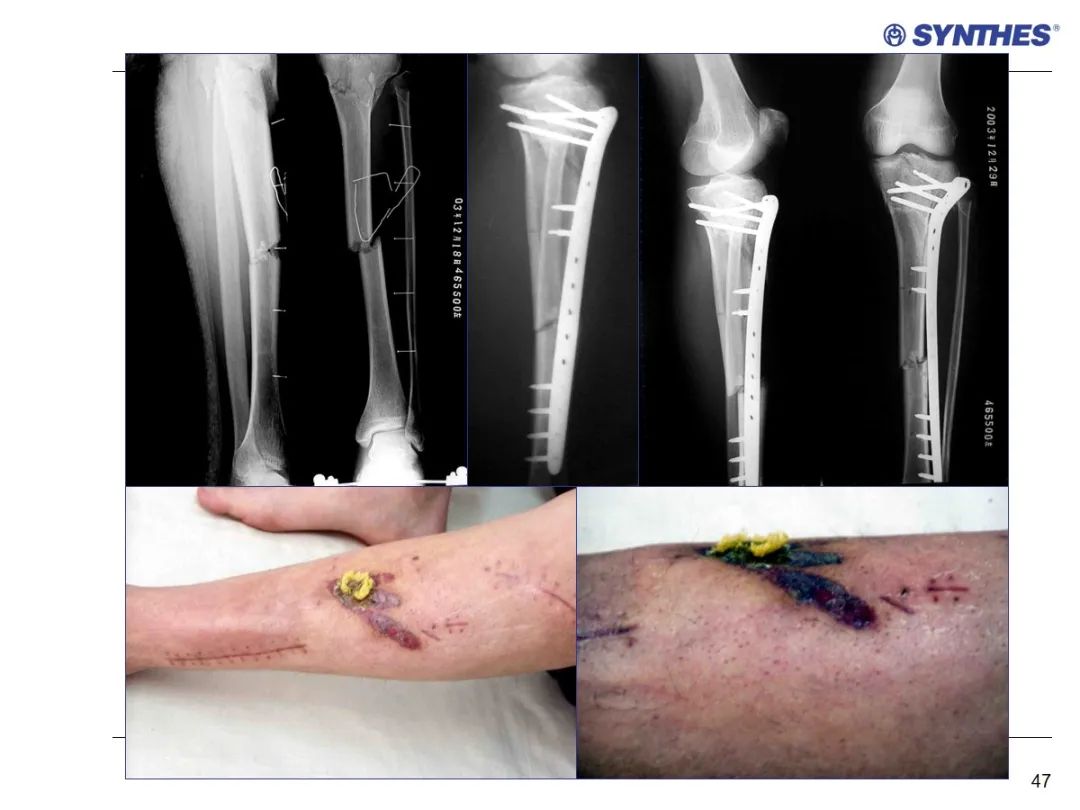

LISS微创固定系统应用技巧,原来如此简单!